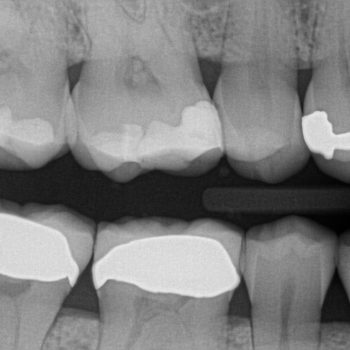

Bitewing X-rays are taken primarily to identify decay between the back teeth. This may be new decay or decay under existing restorations. Decay rarely causes pain, (until it is so extensive that the nerve is infected and root canal treatment is necessary). Our goal is to find decay early when it can be treated with a simple filling or crown. This is the same reason we take a stress test to check for clogged heart arteries before there are symptoms. Often, by the time there are symptoms, the disease is more serious and harder to treat.

You have restorations on almost every back tooth, which puts you at higher risk for decay, hence the once a year bitewings. We don’t take X-rays of the front teeth to check for decay because the teeth are thinner and can be checked visually.